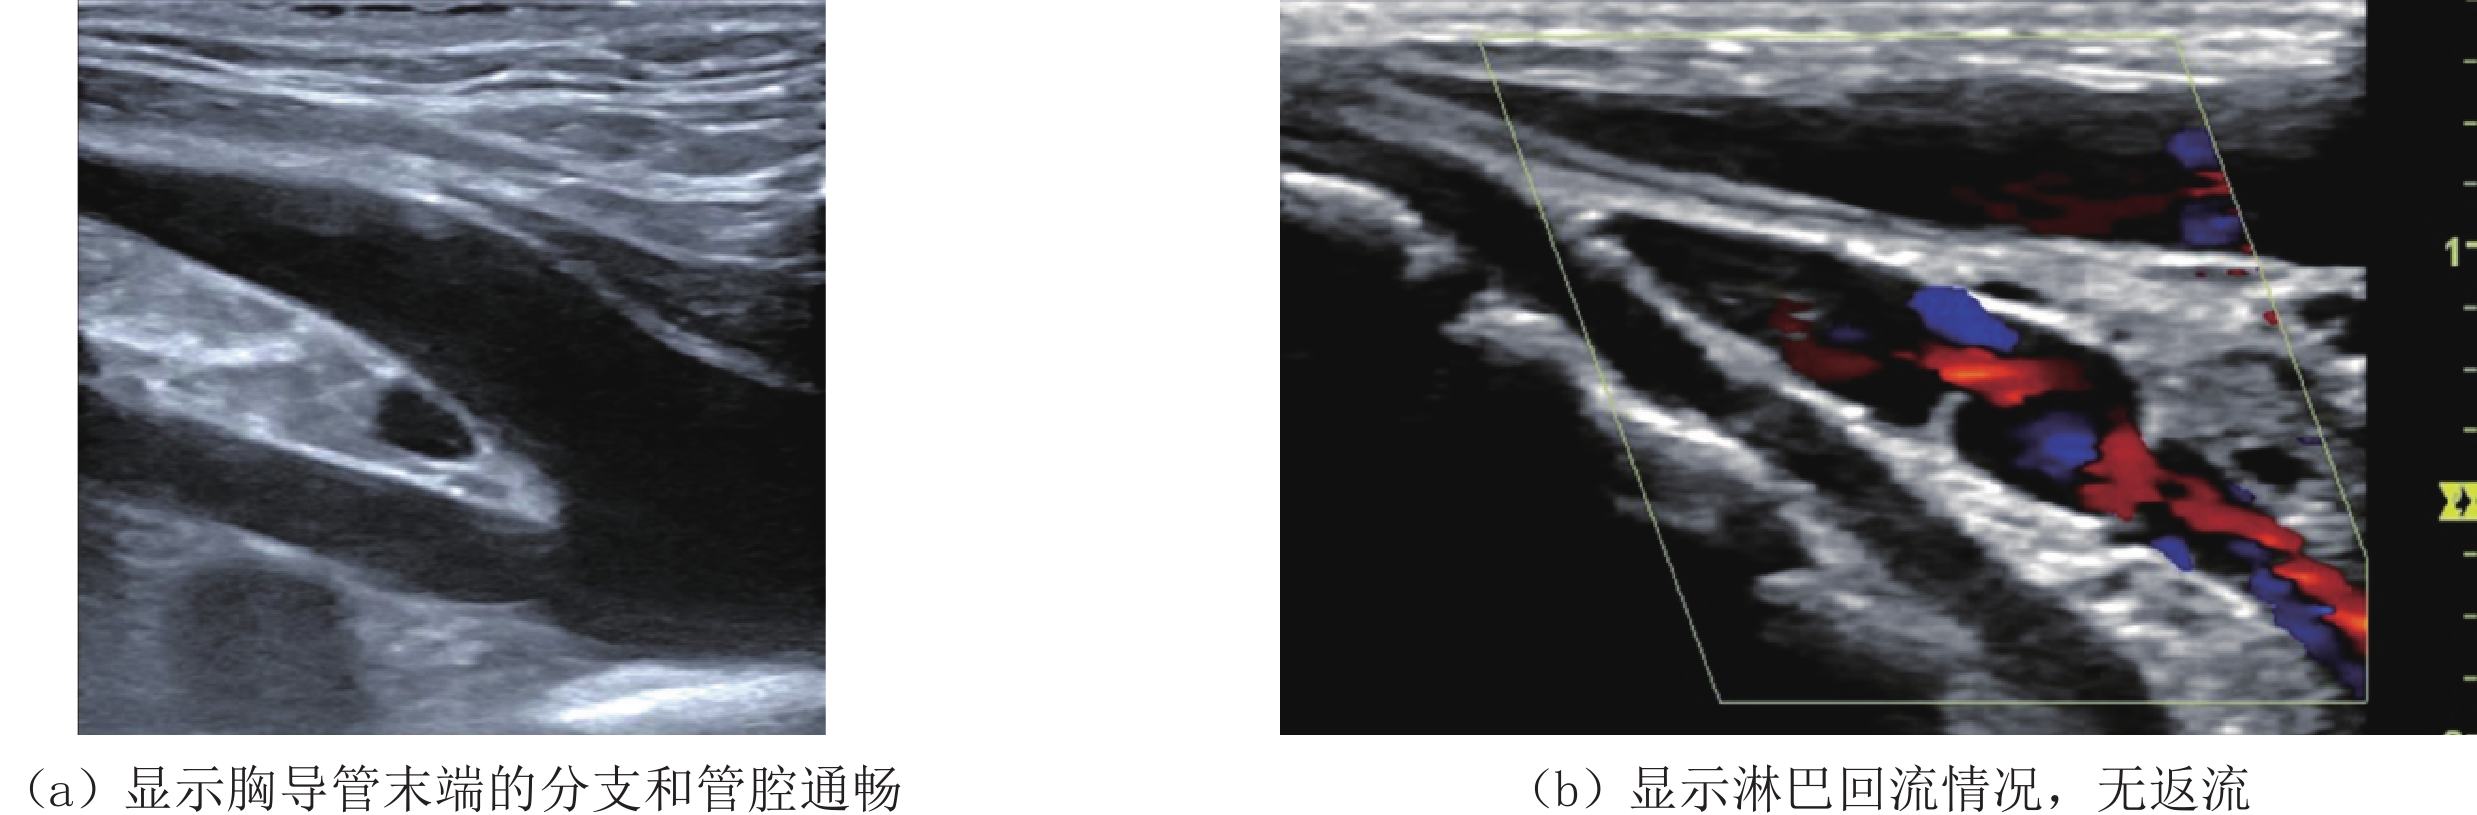

3.4 超声淋巴管成像

超声淋巴管成像(ultrasonic lymphography,ULG),特指采用高频超声探头获取颈部胸导管、胸导管末段及出口显像的影像学方法[11],由于胸导管的结构细长、管壁菲薄、管径狭小且位置隐蔽,常规低频超声的波长较长和图像分辨率较低而显示不佳,而高频超声的短波长明显提高了图像分辨力,可较清晰的显示颈段胸导管的管腔结构、胸导管末端的解剖形态学类型、有无狭窄和淋巴回流以及流入静脉的情况等。

根据高频超声显像特点,胸导管末端可分为5种类型:Ⅰ型,正常型;Ⅱ型,弥漫缩窄性型;Ⅲ 型,末端梗阻型;Ⅳ 型,血栓型;Ⅴ型,反流型。